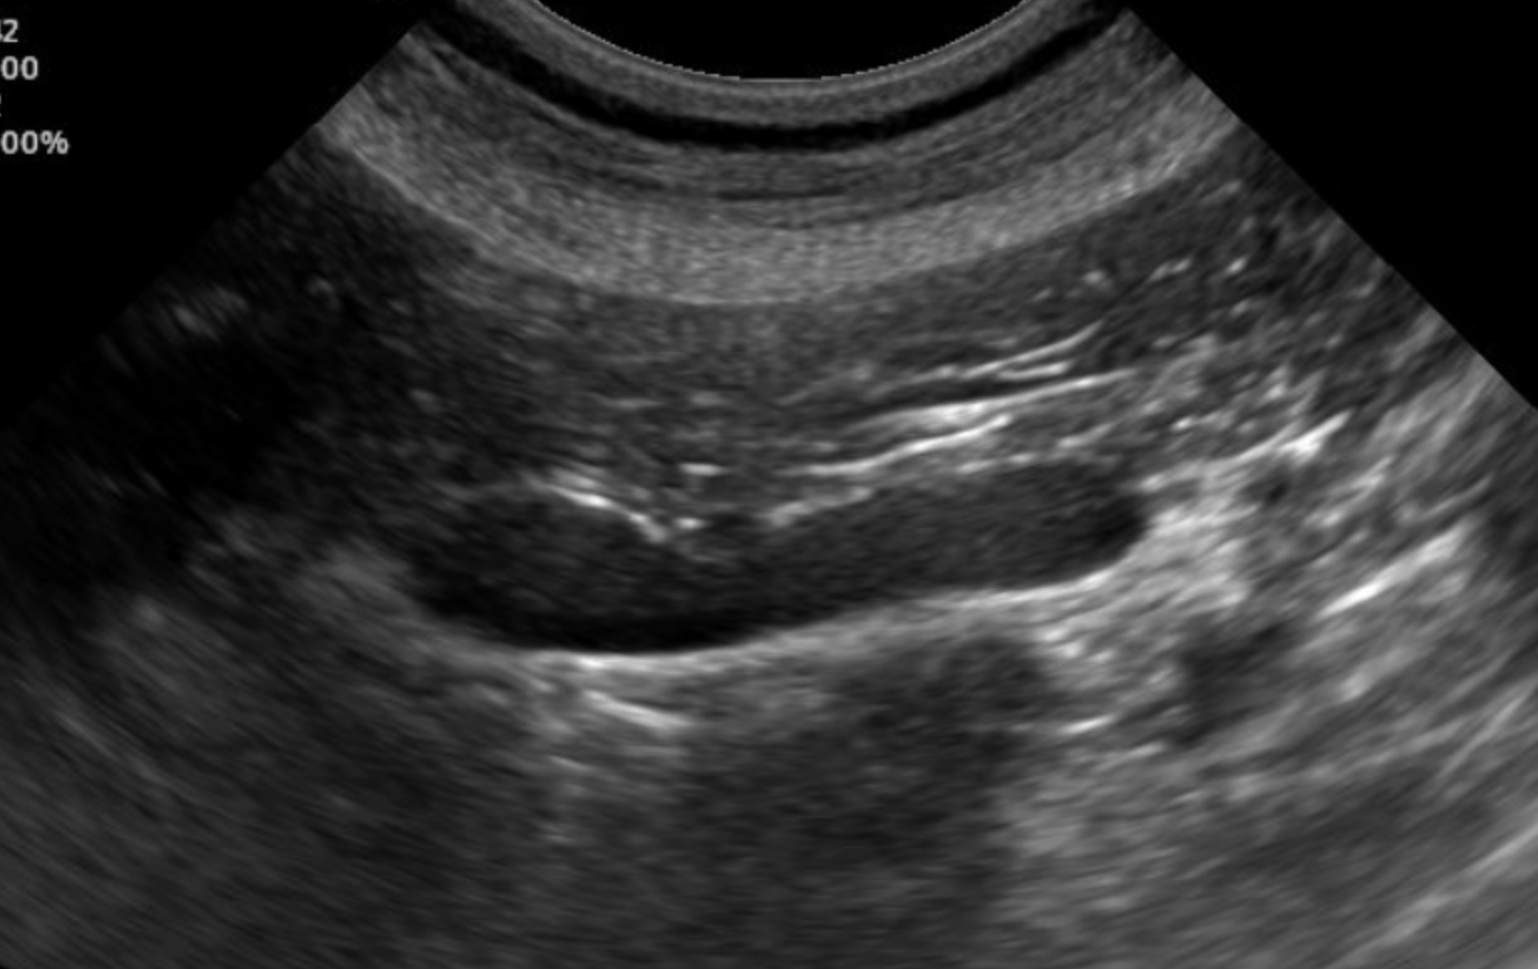

JVI is an independently owned small animal diagnostic imaging service. We offer mobile ultrasound by a board-certified veterinary radiologist to small animal practices in parts of San Mateo County.

Our goal is to provide high quality exams and reports to help veterinarians make informed clinical decisions for their patients while maintaining an efficient workflow.